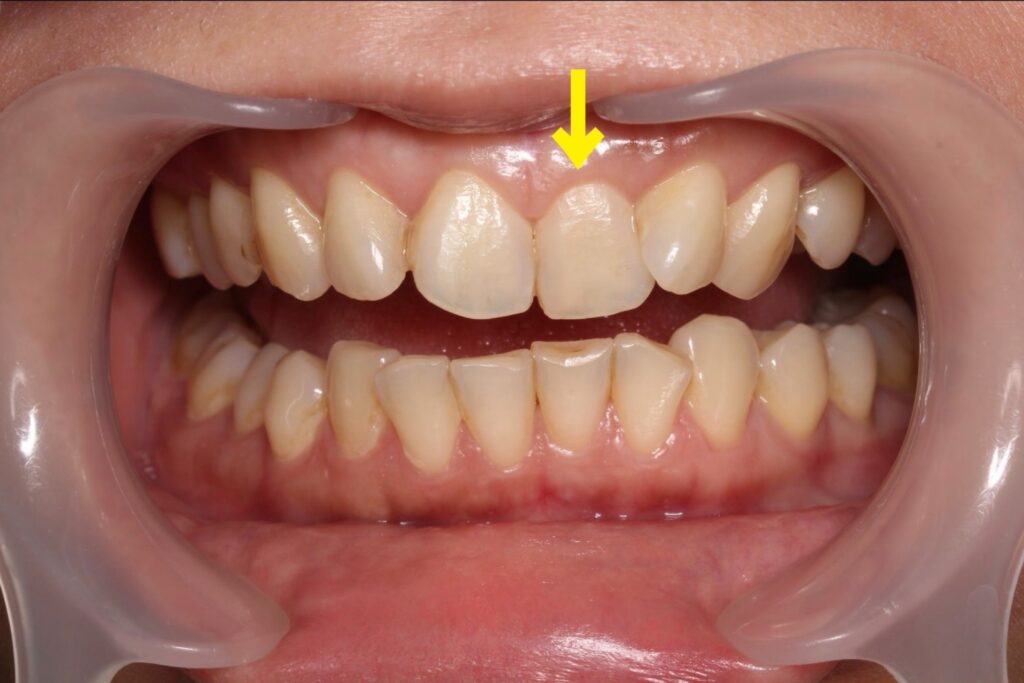

今回ご紹介するのは、右上の前歯(神経のない歯)の変色が気になる患者さまのケースです。

① 根の治療の確認・再治療

レントゲンで確認したところ、他院での過去の根の治療が不十分だったため、再根管治療を行いました。

見た目だけでなく、歯を長持ちさせるための土台を整えることが重要です。